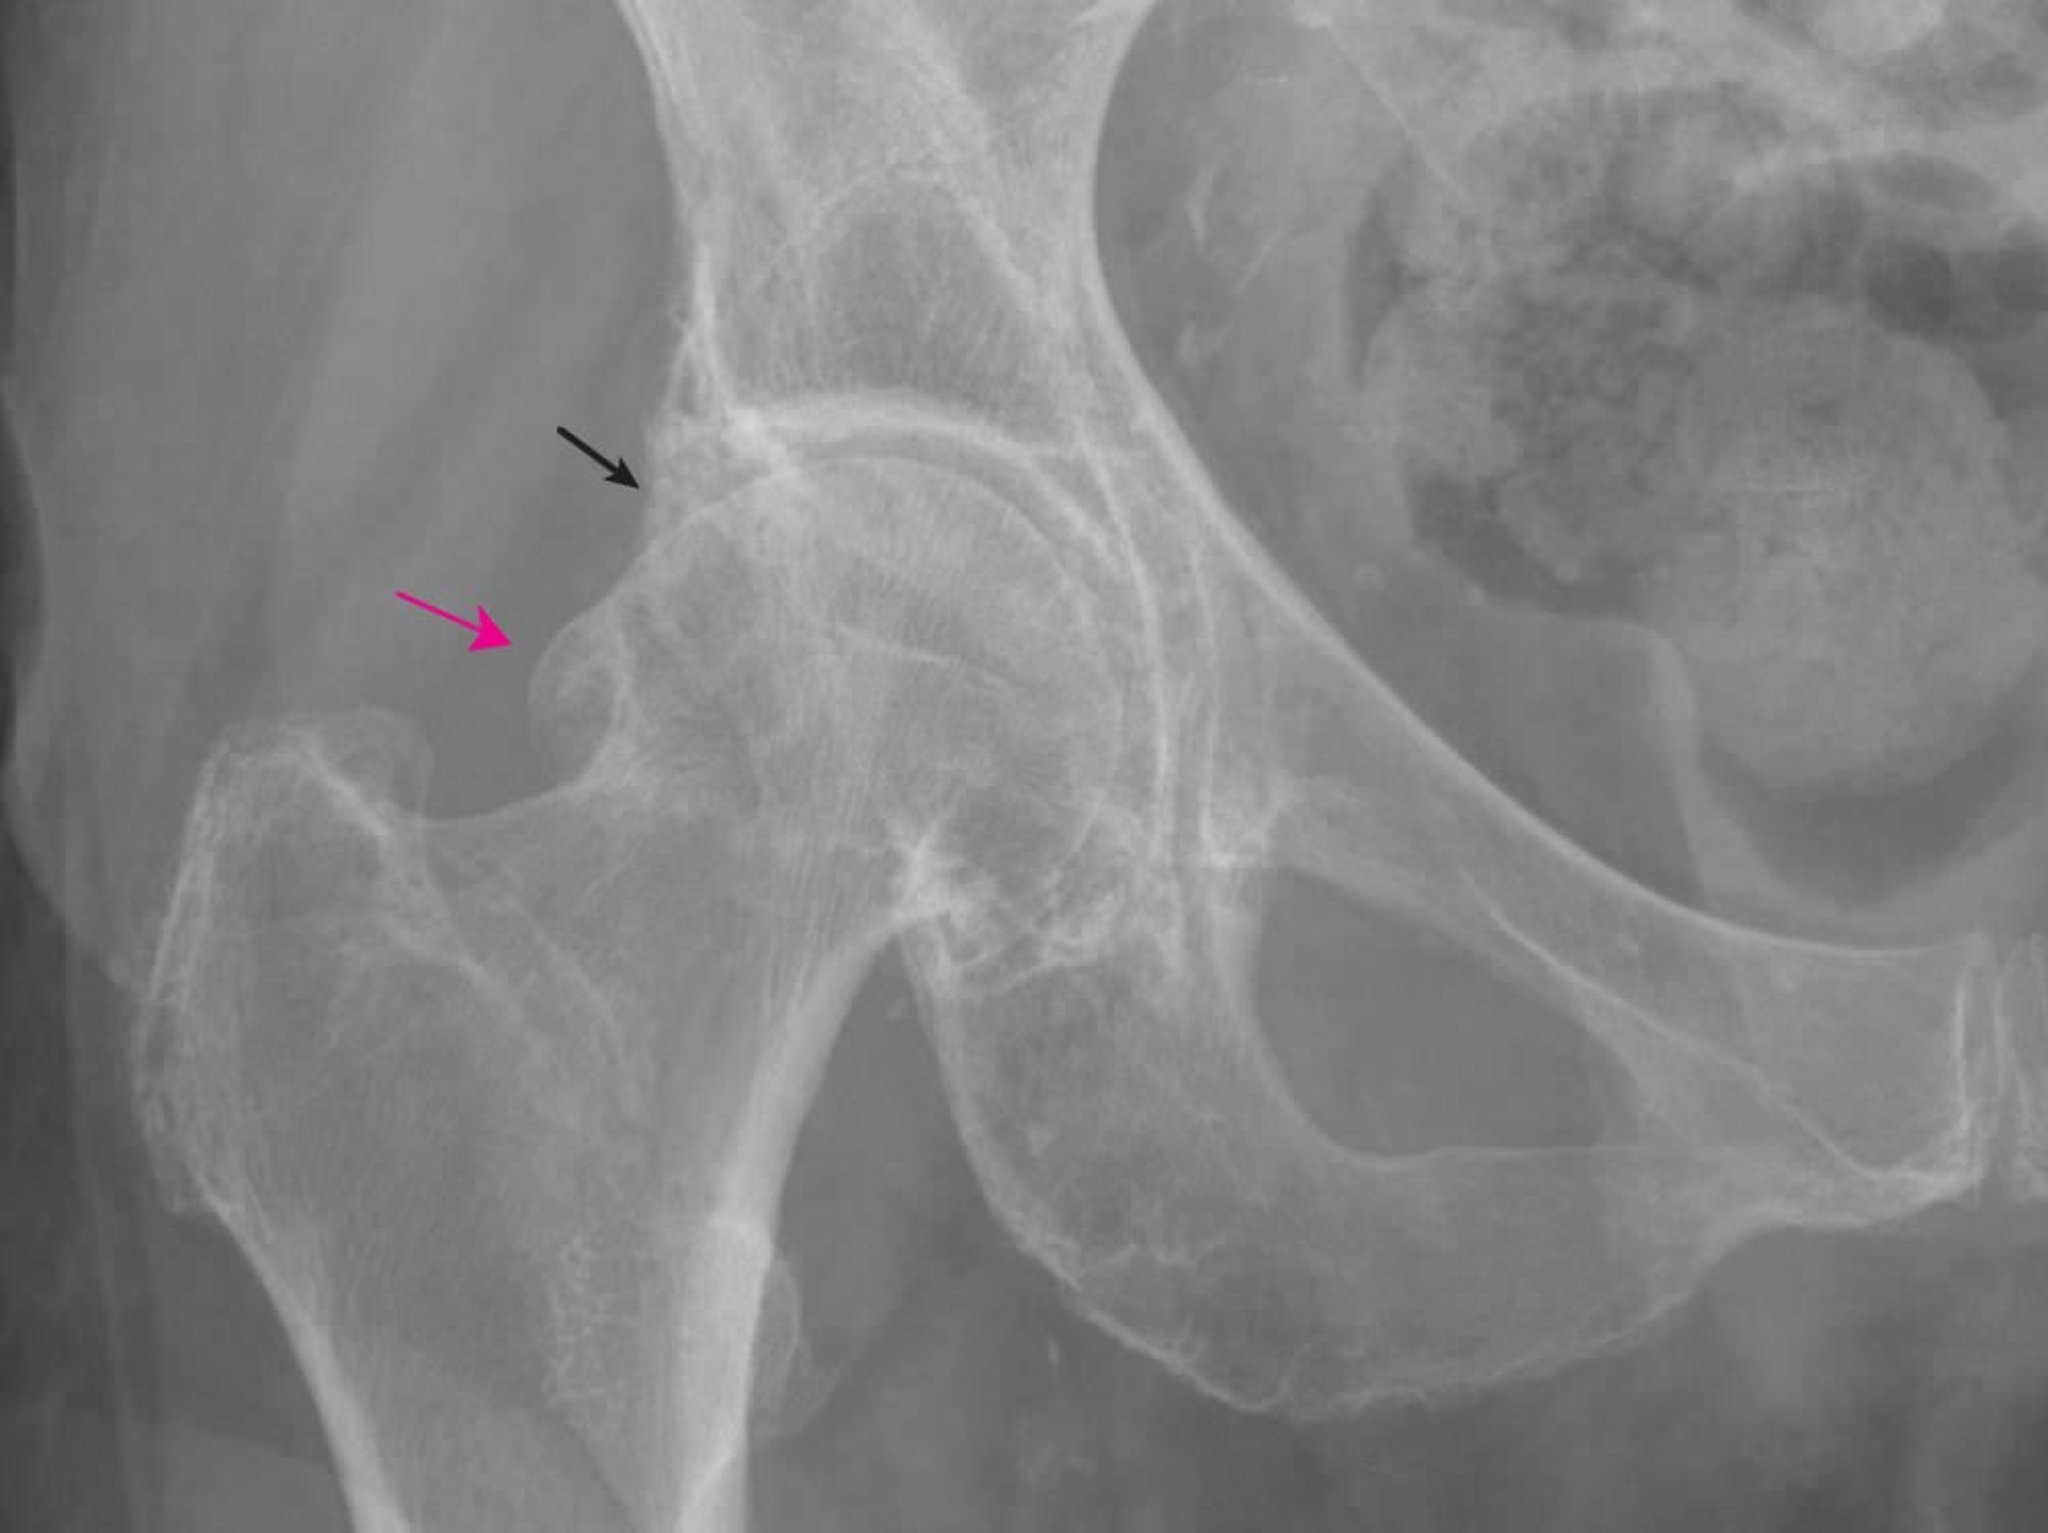

This radiograph shows changes characteristic of osteoarthritis, including large femoral (red arrow) and acetabular (black arrow) osteophytes and some joint space narrowing.

Image provided by Roy Altman, MD.